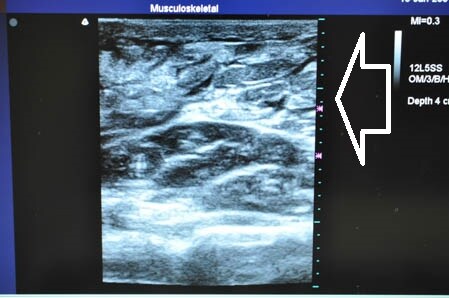

右ちからこぶ。 ↓ ↓ ↓

↓ ↓ ↓